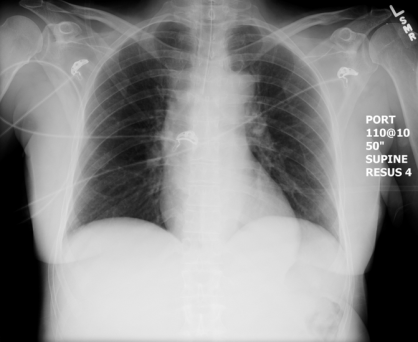

Pre-intubation CXR for the case found here:

(CXR source: http://radiologypics.com/2013/01/25/normal-female-chest-radiograph/)